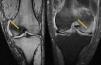

Caso clínicoVarón de 41 años, sin antecedentes de interés, que acudió refiriendo gonalgia derecha, frente a traumatismo mínimo. En la RMN se apreció edema óseo difuso en cóndilo externo. Cuatro meses después surgió edema óseo en cóndilo interno ipsilateral (fig. 1). Posteriormente, en otras resonancias, hallamos nuevo extenso edema óseo, ahora en cóndilo femoral interno de rodilla contralateral, luego en cóndilo externo y dolor en tobillo derecho, en cuya RMN también se apreciaba edema óseo, en astrágalo (figs. 2 y 3). Se instauró tratamiento con AINE, y carga parcial, siendo ineficaz.

En el diagnóstico diferencial es interesante su distinción respecto de la algodistrofia de Südeck, distrofia simpático refleja o síndrome de dolor regional complejo. Esta entidad cursa con dolor tras un evento traumático, a veces de poca intensidad, presentando alodinia (o dolor intenso en respuesta a estímulos no dolorosos), hiperalgesia, así como, trastornos vasomotores de compromiso vegetativo. En una osteoporosis transitoria migratoria no se manifiesta este cortejo vegetativo. Por otro lado, el edema medular óseo se presenta como un patrón de imagen en la RMN. caracterizado por hiposeñal en T1 e hiperseñal en STIR T2 en médula ósea. Cuando este edema aparece en varias articulaciones, sin imágenes de osteonecrosis, y no de forma aislada, estaríamos ante una osteoporosis transitoria migratoria.